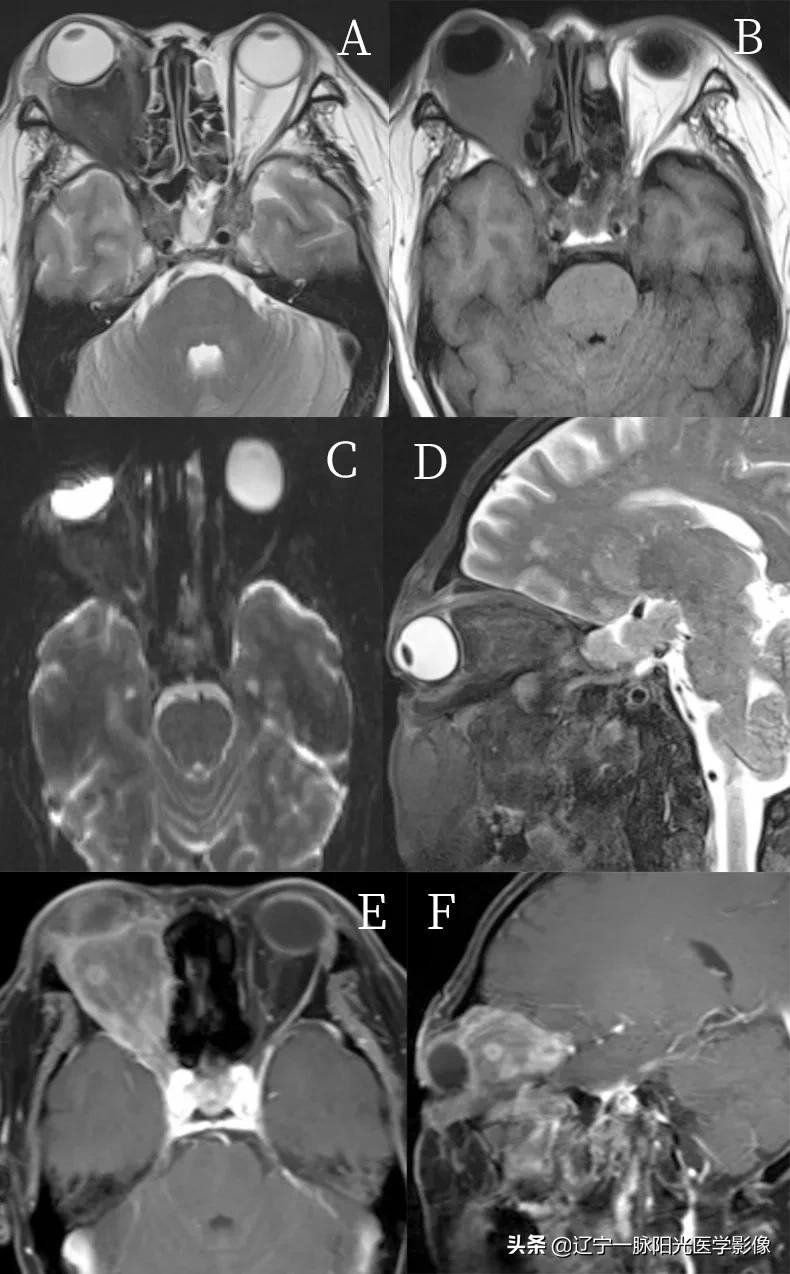

简要病史:男 44 岁,主诉:右眼视物模糊 2 年。

影像所见;:

图 A、B 轴位示右侧眼球稍向前突,球后充盈团块状软组织信号影,范围约 4.3 cm×3.5 cm, T1WI、T2WI 呈低信号

图 C 示 DWI 亦呈低信号

图 E、F 增强后呈不均匀明显强化,其内见环行强化,病灶包绕右侧视神经及眼肌

病理诊断:炎性假瘤